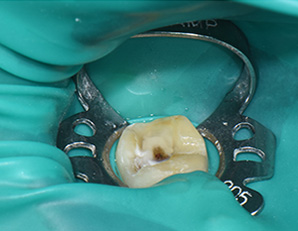

셋추가 감염방지를 위한 러버댐 장착 -